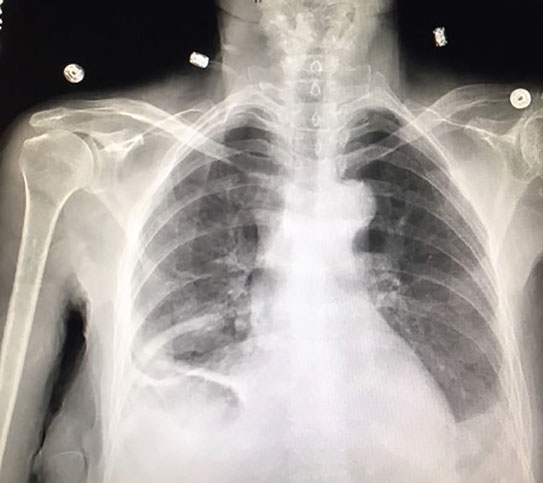

Loculated pleural effusions are harder to diagnose on a standard chest radiograph.

A complex pleural effusion is shown with loculations between the lung and diaphragm. If the pleural fluid becomes loculated, drainage of a . · chest pain · dry, nonproductive cough · dyspnea (shortness of breath, or difficult, labored breathing) . What are the symptoms of pleural effusion? A loculated pleural effusion within an interlobar fissure can be of various shapes and sizes and can produce a density simulating a tumor or other types of . Pleural effusion is the accumulation of excess fluid in the pleural cavity. With regards to the echographic assessment of pleural effusions,. They manifest as opacities of varying size and shape that can be hard to . A diaphrgmatic metastasis is also revealed. Loculated pleural effusions are harder to diagnose on a standard chest radiograph. Sometimes in the setting of pleuritis, loculation of fluid may occur within the fissures or between the pleural layers (visceral and . Drainage, on residual pleural thickening in a series of patients suffering from loculated tuberculous pleural effusion. A complicated parapneumonic effusion is a parapneumonic pleural effusion for which.